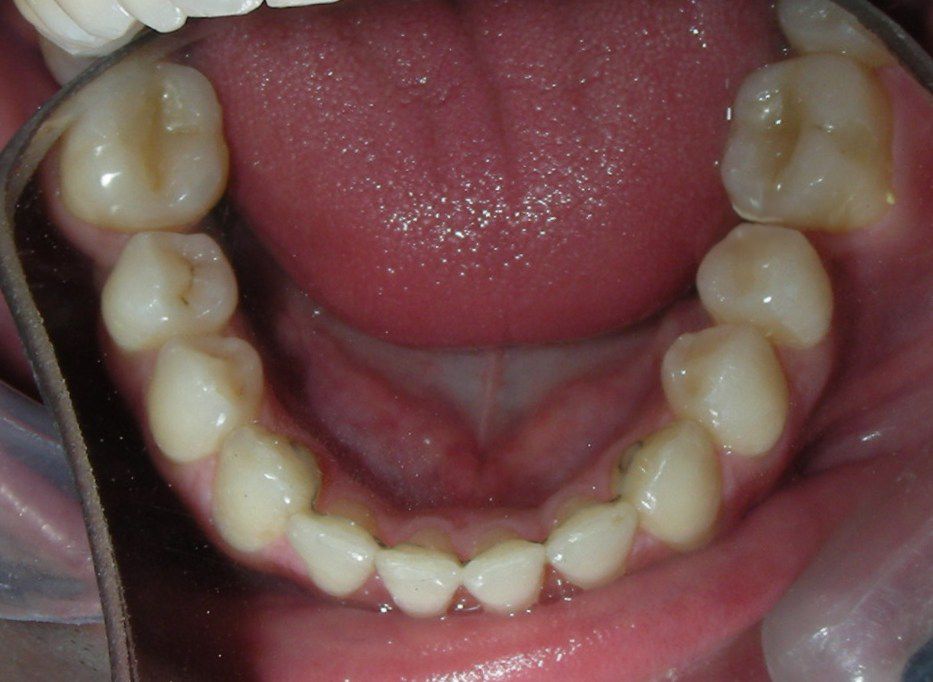

Was installed a Hyrax-type 10mm palatal expander of the Brazilian trademark Morelli® , modified by the author to be adapted to receive TADs microscrews, in order to initiate maxillary disjunction with MARPE (Mini-implant Assisted Rapid Palatal Expansion), TADS was installed with skeletal anchorage placed bilaterally having as references the roots of the maxillary canines and first premolars. Prior to insertion, local infiltrative anesthesia was administered using 2% lidocaine hydrochloride with 1:100,000 epinephrine. A total dose of approximately 0,8 mL per side (cortical infiltration technique). The TADs were inserted under aseptic conditions using a manual driver. Microscrew Evolution 1,6 Ø x 10 mm from the Argentine brand Odontit® . The Hyrax expander was then fitted and activated after 48 hrs .

Protocol of one activation per day was followed for a period of three weeks where the first clinical and radiographic evaluation was performed, showing clear signs of skeletal expansion, including the presence of a midline diastema. One more week of activations was added with a total of 28. The patient reported moderate headache during the first week of activation.

Having successfully achieved the expansion, we proceed to the intrusion of the posterior superior sectors, modifying the Hyrax by adding anchoring hooks at the buccal level of the first premolars. Using the Hyrax as anchorage, we sought a parallel intrusion. This could be replaced by a palatal bar. TADs were installed bilaterally at the mesial level of the first molars, inserting them as parallel as possible to the roots.